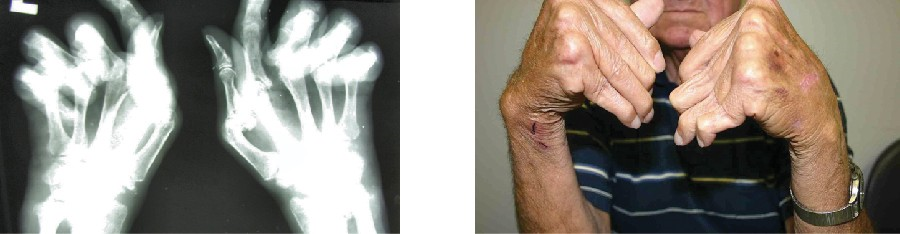

The most common chronic inflammatory joint disease is rheumatoid arthritis (RA) (Figure 15.12) and it is still a major medical challenge because of unsolved questions related to the environmental and genetic causes of the disease. RA involves type III hypersensitivity reactions and the activation of CD4 T cells, resulting in chronic release of the inflammatory cytokines IL-1, IL-6, and tumor necrosis factor-α (TNF-α). The activated CD4 T cells also stimulate the production of rheumatoid factor (RF) antibodies and anticyclic citrullinated peptide antibodies (anti- CCP) that form immune complexes. Increased levels of acute-phase proteins, such as C-reactive protein (CRP), are also produced as part of the inflammatory process and participate in complement fixation with the antibodies on the immune complexes. The formation of immune complexes and reaction to the immune factors cause an inflammatory process in joints, particularly in the hands, feet, and legs. Diagnosis of RA is based on elevated levels of RF, anti- CCP, quantitative CRP, and the erythrocyte sedimentation rate (ESR) (modified Westergren). In addition, radiographs, ultrasound, or magnetic resonance imaging scans can identify joint damage, such as erosions, a loss of bone within the joint, and narrowing of joint space.

The radiograph (left) and photograph (right) show damage to the hands typical of rheumatoid arthritis.

Figure 15.12 The radiograph (left) and photograph (right) show damage to the hands typical of rheumatoid arthritis. (credit right: modification of work by “handarmdoc”/Flickr)